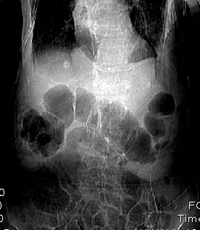

椎体压缩性骨折,结肠淤张,胀气说明肯定骨折.

椎体压缩骨折,结肠淤张,应该肯定,交感神经有损伤.